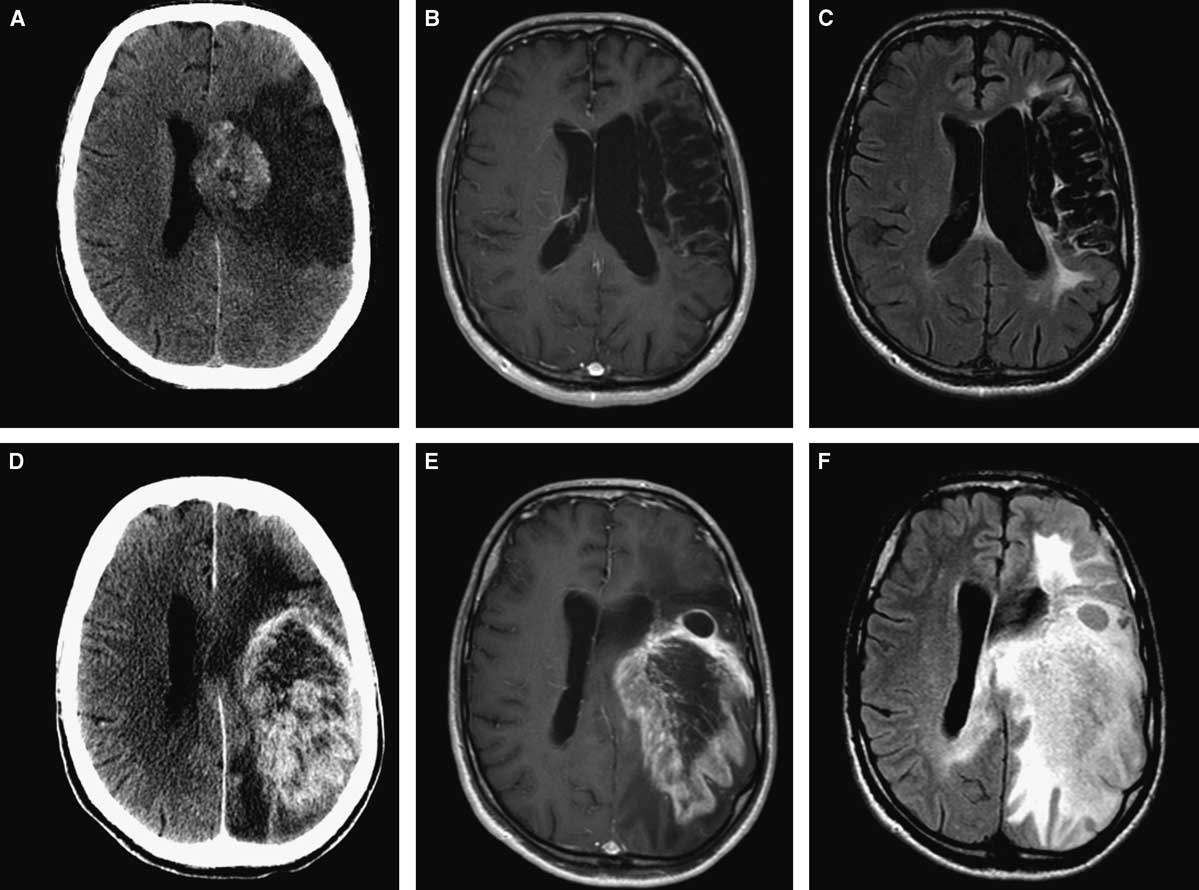

A 59-year-old man presented with a progressive decline in speech. Past medical history was significant for a left middle cerebral artery (MCA) territory stroke 8 years prior to the current presentation (Figure 1A,B,C). Neurologic examination demonstrated global aphasia and preexisting right-sided hemiplegia. Imaging showed a large enhancing lesion within the infarcted area (Figure 1D,E,F). Computed tomography (CT) of the chest, abdomen, and pelvis did not reveal any evidence of other tumours. A presumed diagnosis of a primary neoplastic lesion was made, and the patient underwent craniotomy and subtotal resection of the lesion. There were no intra- or postoperative complications. Final histopathology was consistent with a WHO grade IV glioblastoma. The patient was referred for radiation therapy. His Karnofsky score at 1-month follow-up was 40%.

Figure 1 Initial neuroimaging at the time of stroke (A,B,C): axial CT (A), axial MRI with gadolinium (B), and FLAIR sequence (C). Eight years later (D,E,F): axial CT (A), axial MRI with gadolinium (B), and FLAIR sequence (C) showing large intra-axial tumour involving the same area affected by ischemia.